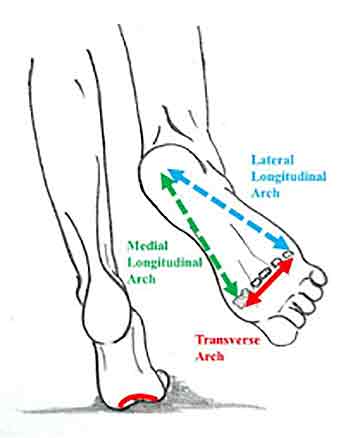

Ankle and foot pain

Much misunderstood, the foot is of course the foundation for all that rests upon it. The foot is a composite of many bones and tendons most of which arise from the calf and front of the shin. Mostly what happens is a collapse of the arch. This due to the design that you were born with and due to shoes which do not support the heel properly. People with a lordosis (forward arching of the low back) will have increased inner rotation of the knees and a consequent dropping of the foot arch. There is a long list of conditions that affect the feet, too many to list here.